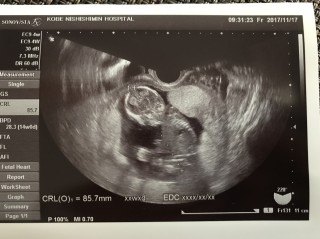

初めての経腹エコー。検診が1か月ぶりで、つわりも軽い私はちゃんとお腹の中にいるのかとすごく不安でしたが、かなり人の形になっていてびっくりしました!8.5cmでした。背骨や内臓も見えたし、指も5本見えてとても感動しました。かわいくてたまらないです。動画をUSBにしてもらえたので毎日見ています。指しゃぶりをしたり、あぐら?を組み替えたりしていました!

今日はなかなか心拍が見えづらい角度で、不安でしたが、無事見えやすい角度で確認することができました^_^ホッと一安心です。 お尻の辺りがエコーで見えにくくハッキリ映ってませんが大体8~9センチぐらいやなーって言われた^^ 頭は28.3ミリとゆーことで14週相応と言われましたが、身長が8~9センチが平気なのかどーなのか言ってもらえなかったのですが、元気にしてるとのことです^_^